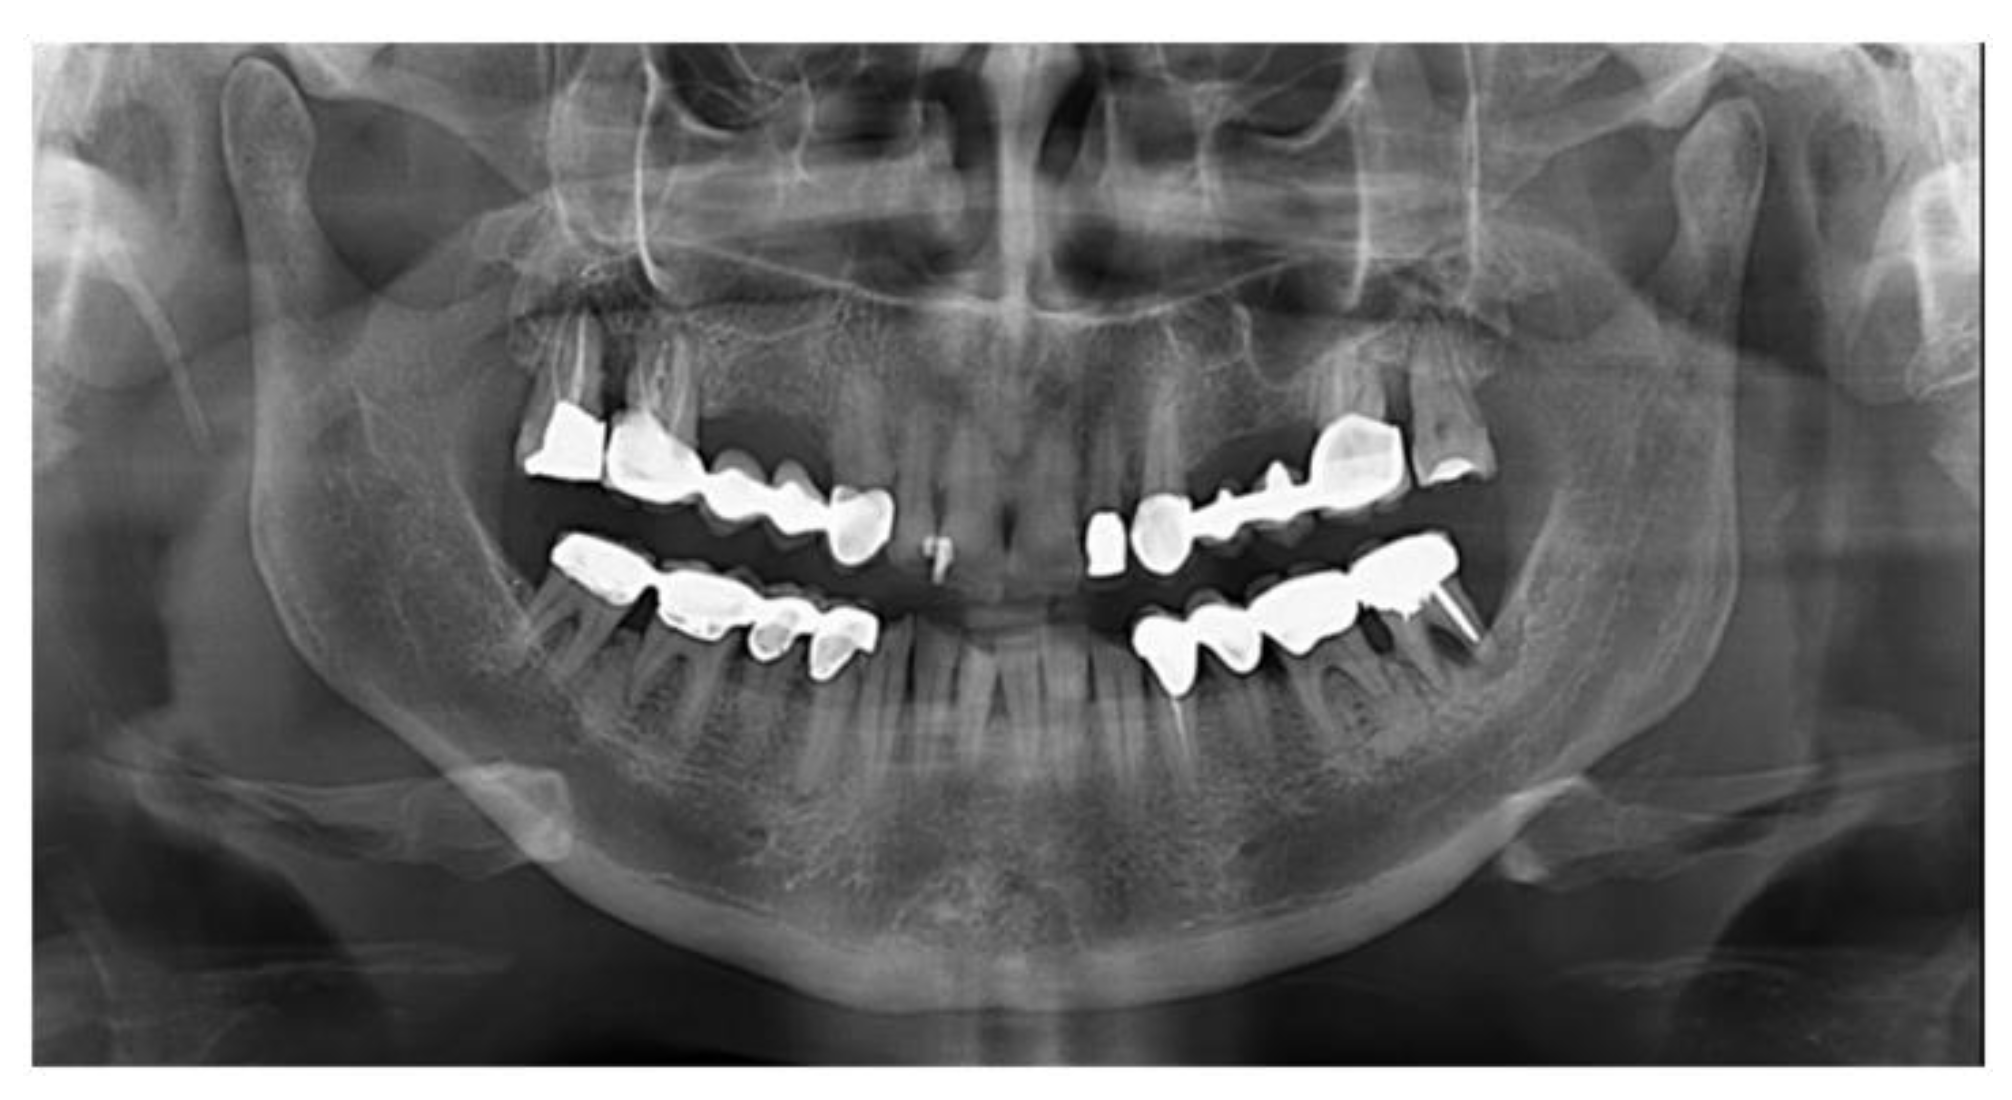

2. Materials and Methods

2.1. Surgical Procedures